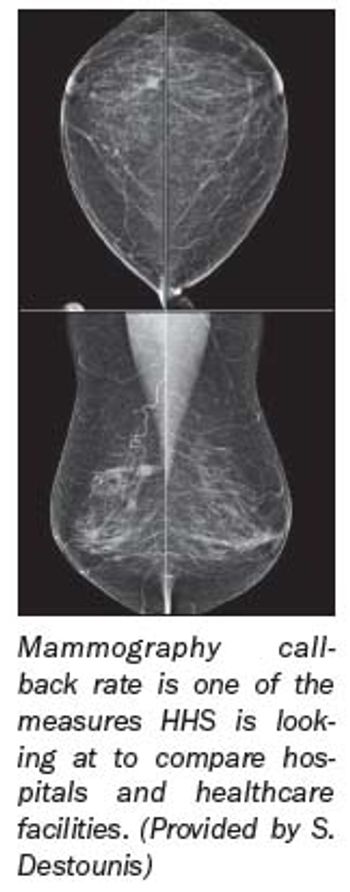

With all the doom and gloom surrounding mammography-lower reimbursement, high threat of malpractice lawsuits-it's easy to assume residents would shy away from the field.

States across the country are reducing funding for their breast cancer screening programs or tightening eligibility requirements, leaving many women without their annual screening mammograms. In all, 17 states have cut back on the programs to help balance their budgets.